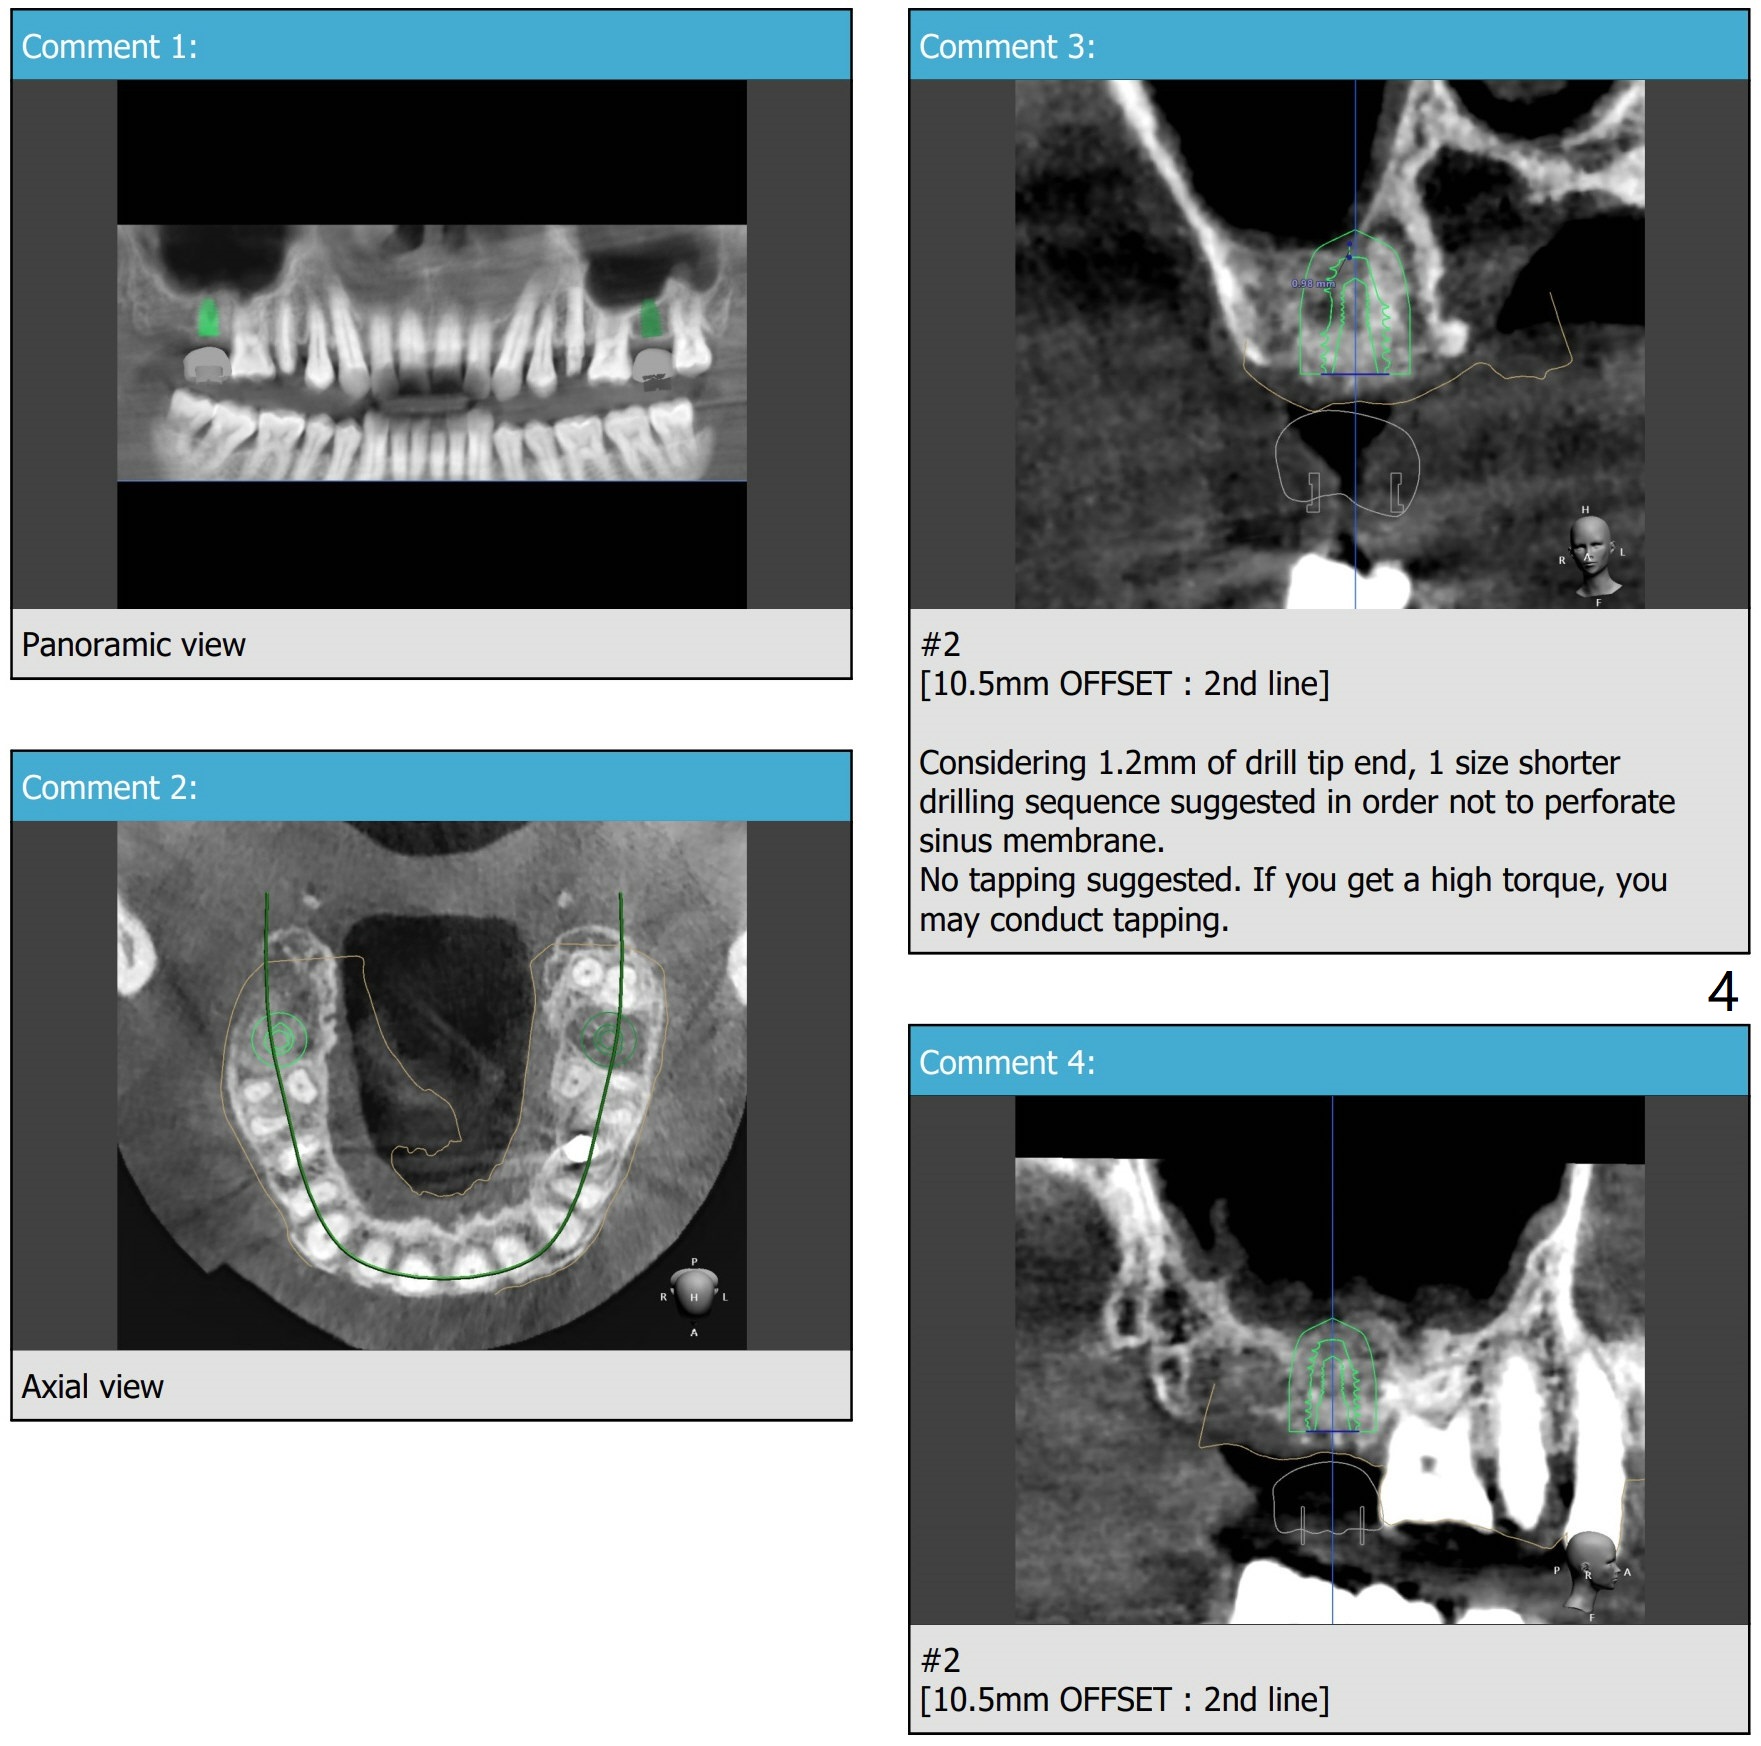

提升目的

Return to No Deviation  位点保留后

Xin Wei, DDS, PhD, MS 1st edition 10/09/2020, last revision 10/26/2020